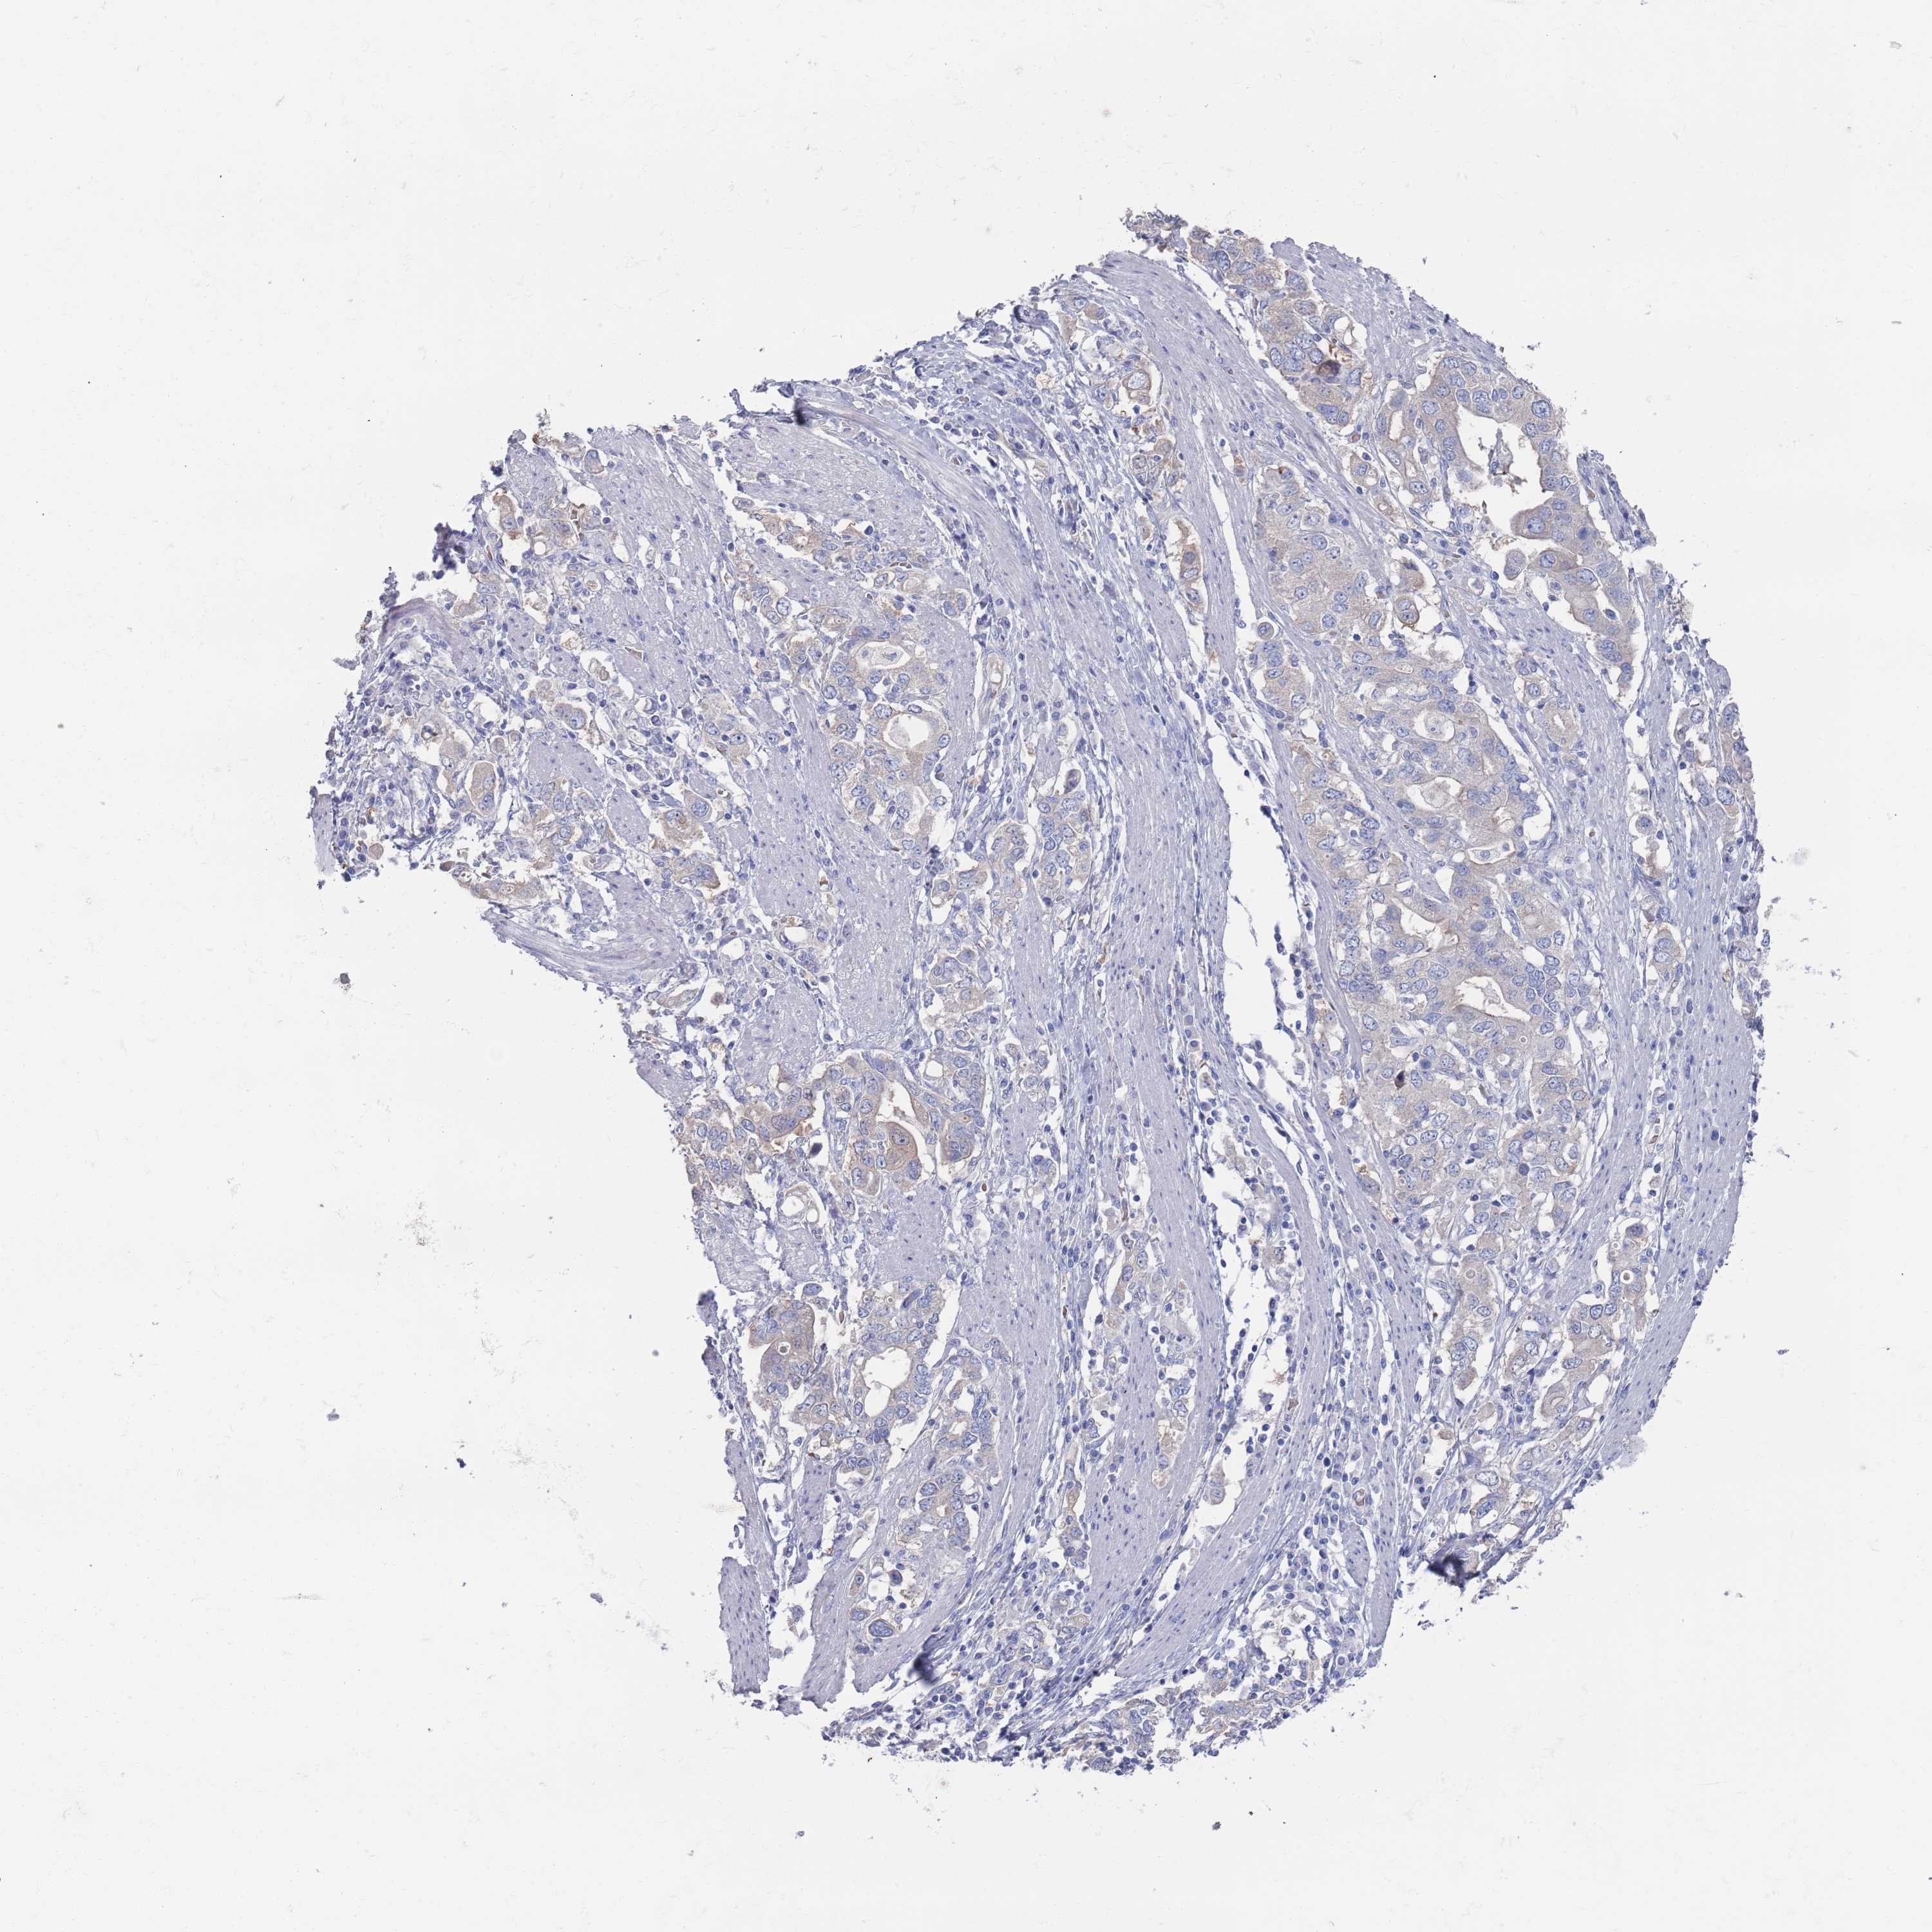

STOMACH CANCER - Protein expressioni

A mouse-over function shows sample information and annotation data. Click on an image to view it in a full screen mode. Samples can be filtered based on level of antibody staining by selecting one or several of the following categories: high, medium, low and not detected. The assay and annotation is described here.

Note that samples used for immunohistochemistry by the Human Protein Atlas do not correspond to samples in the TCGA dataset.

Antibody stainingi

Antibody staining in the annotated cell types in the current human tissue is reported as not detected, low, medium, or high, based on conventional immunohistochemistry profiling in selected tissues. This score is based on the combination of the staining intensity and fraction of stained cells.

Each image is clickable and will lead to virtual microscopy that enables deeper exploration of all samples and also displays staining intensity scores, fraction scores and subcellular localization as well as patient and tissue information for each sample.

Antibody HPA039561

Antibody HPA048126

Staining

High

Medium

Low

Not detected

Intensity

Strong

Moderate

Weak

Negative

Quantity

>75%

75%-25%

<25%

None

Location

Nuclear

Cytoplasmic/membranous

Cytoplasmic/membranous,nuclear

Adenocarcinoma, NOS